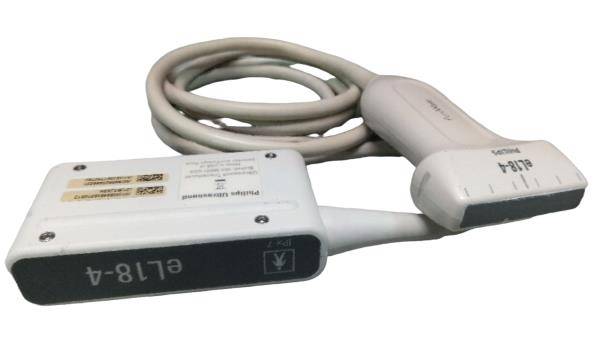

Versatile Probes for Comprehensive Assessment

This system comes with both transvaginal and linear probes, allowing for versatility in patient assessments. For instance, transvaginal probes are particularly useful for gynecological examinations. However, linear probes are ideal for surface-level examinations and vascular assessments. Therefore, having multiple probes enhances the scanner's utility, making it suitable for various medical settings.